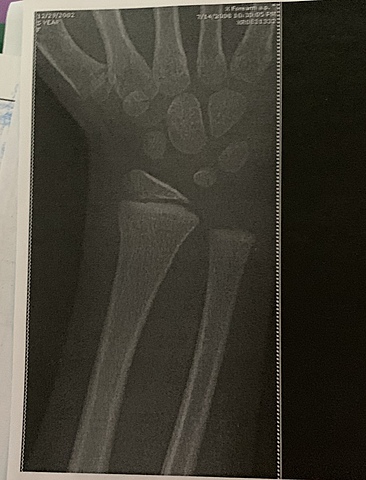

• Broke My Arm

Broke My Arm

I broke my arm in the summer of 2008 from crashing my bicycle on a bike trail behind Deanna Rose Farmstead.